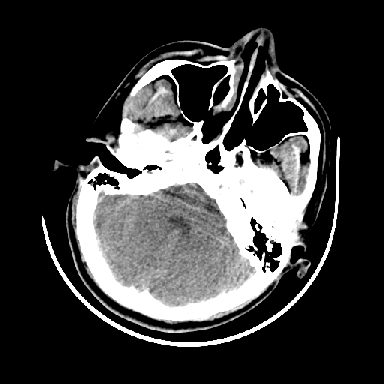

以下是引用dyqct在2007-4-9 11:18:00的发言:[br]左额颞顶叶、基底节区呈大片低密度区,累及皮质,中度占位效应,同侧侧脑室旁见小片状高密度区,边界清楚。中线结构向右弧形移位。右侧侧脑室略扩张。[br]考虑:1、左侧额颞顶叶、基底节区缺血性脑梗塞(符合大脑中动脉供血区)伴出血。[br] 2、建议增强扫描进一步检查。

以下是引用卜一在2007-4-9 15:08:00的发言:[br][br] 左侧额颞顶叶、基底节区缺血性脑梗塞(符合大脑中动脉供血区)伴出血。原因:多考虑外伤后出血,形成血栓所致。 [br]